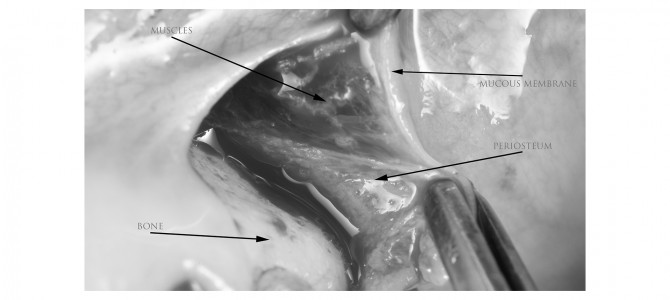

Continuiamo con le basi di gestione dei tessuti molli. Di recente abbiamo discusso del taglio di scarico in mandibola posteriore, penso che sia giusto ora parlare di ciò che salta fuori quando fai un taglio di scarico verticale nel fornice mascellare. Anche se sembra…

IL TAGLIO DI SCARICO NELLA MANDIBOLA POSTERIORE – LA BUGIA CHE MI HANNO RACCONTATO ALL’UNIVERSITÀ!